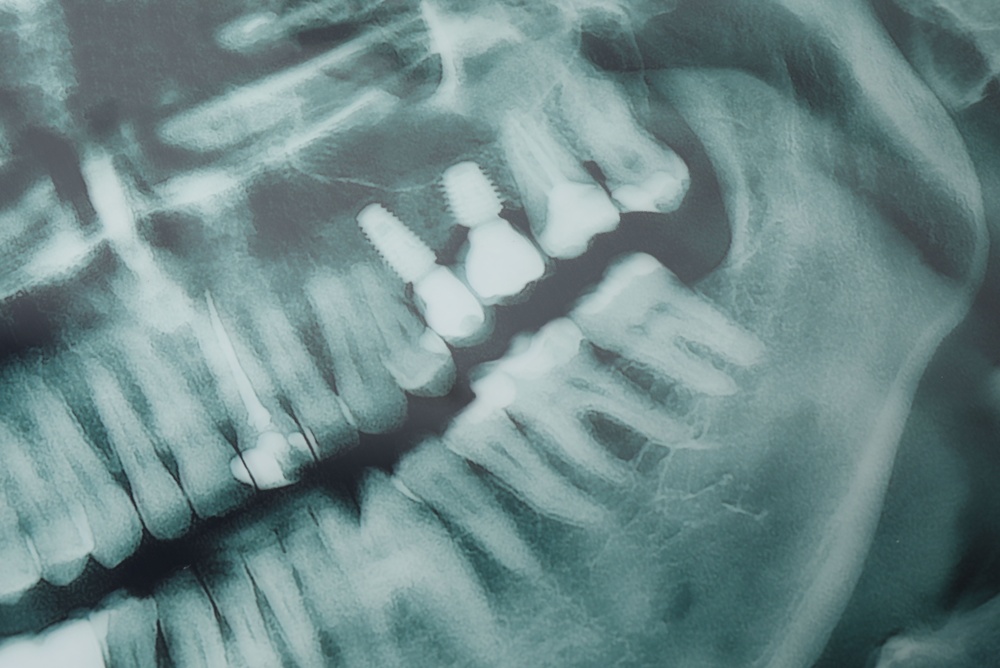

Getting a front tooth implant involves several steps. First, a dental surgeon inserts a titanium post into your jawbone, acting as an artificial tooth root. After the implant has integrated with the bone, an abutment is attached, onto which a custom-made crown is placed, replacing the visible part of the tooth.